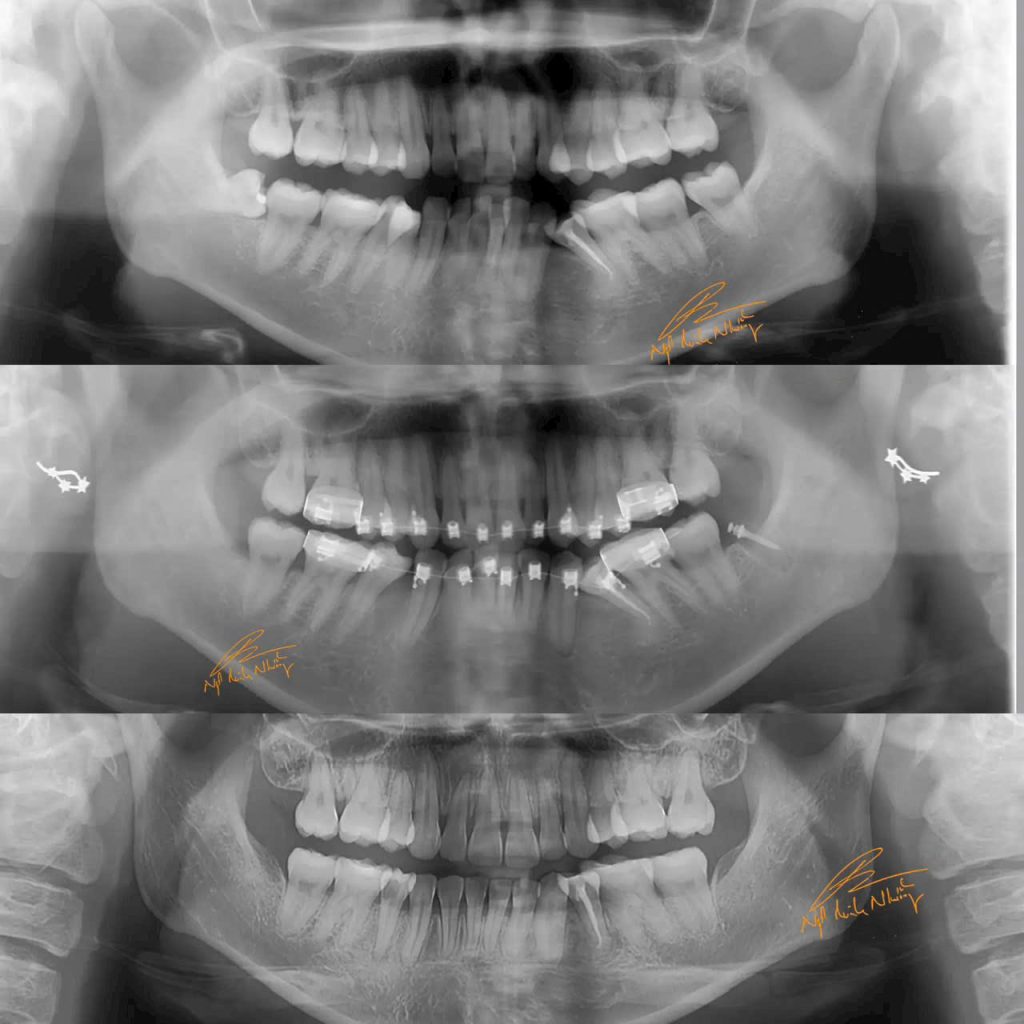

Một ca tiếp theo thay đổi E line, tương quan mũi-môi-cằm nhờ niềng răng: